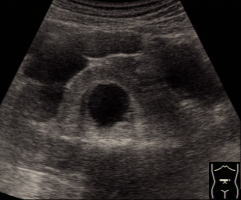

CT掃描可清晰地描繪出腎臟的輪廓,但並非必不可少。對於盆腔融合腎或位於脅腹部者,插入輸尿管導管的平片將為診斷提供第一條線索。逆行造影將顯示腎盂的位置及因有感染或梗阻所致改變。腎閃爍攝影術可顯示出腎塊及其輪廓,如同超聲影象一般。